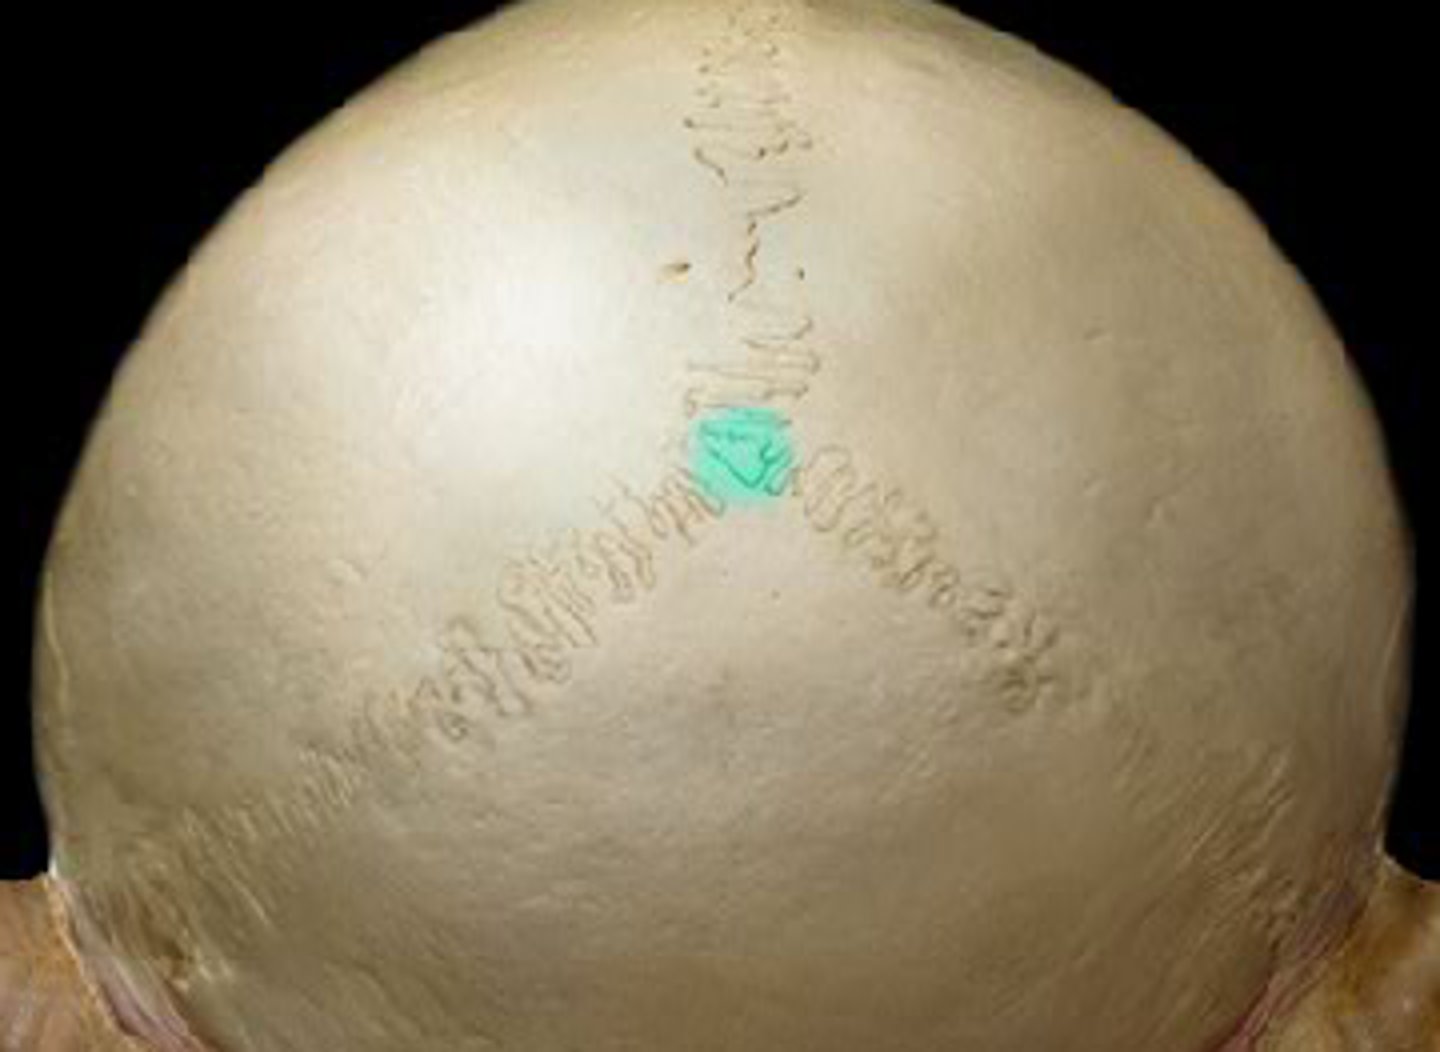

bregma

sagittal suture

lambda